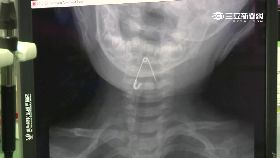

女星許維恩10月大女兒日前傳出誤吞別針,出現臉色慘白...

許維恩女兒誤吞別針 醫示警這4物最危險

藝人許維恩在2021年閃嫁小6歲王家梁,去年他們也生...

女兒誤吞別針缺氧吐血絲 許維恩:好失敗

藝人許維恩2021年與藝人王家梁結婚,去年6月寶貝女...

嬰喉嚨卡2cm別針 臉脹紅嚎哭險死

新衣服吊牌上的別針,差點要了男嬰的命!台中一名十個月...